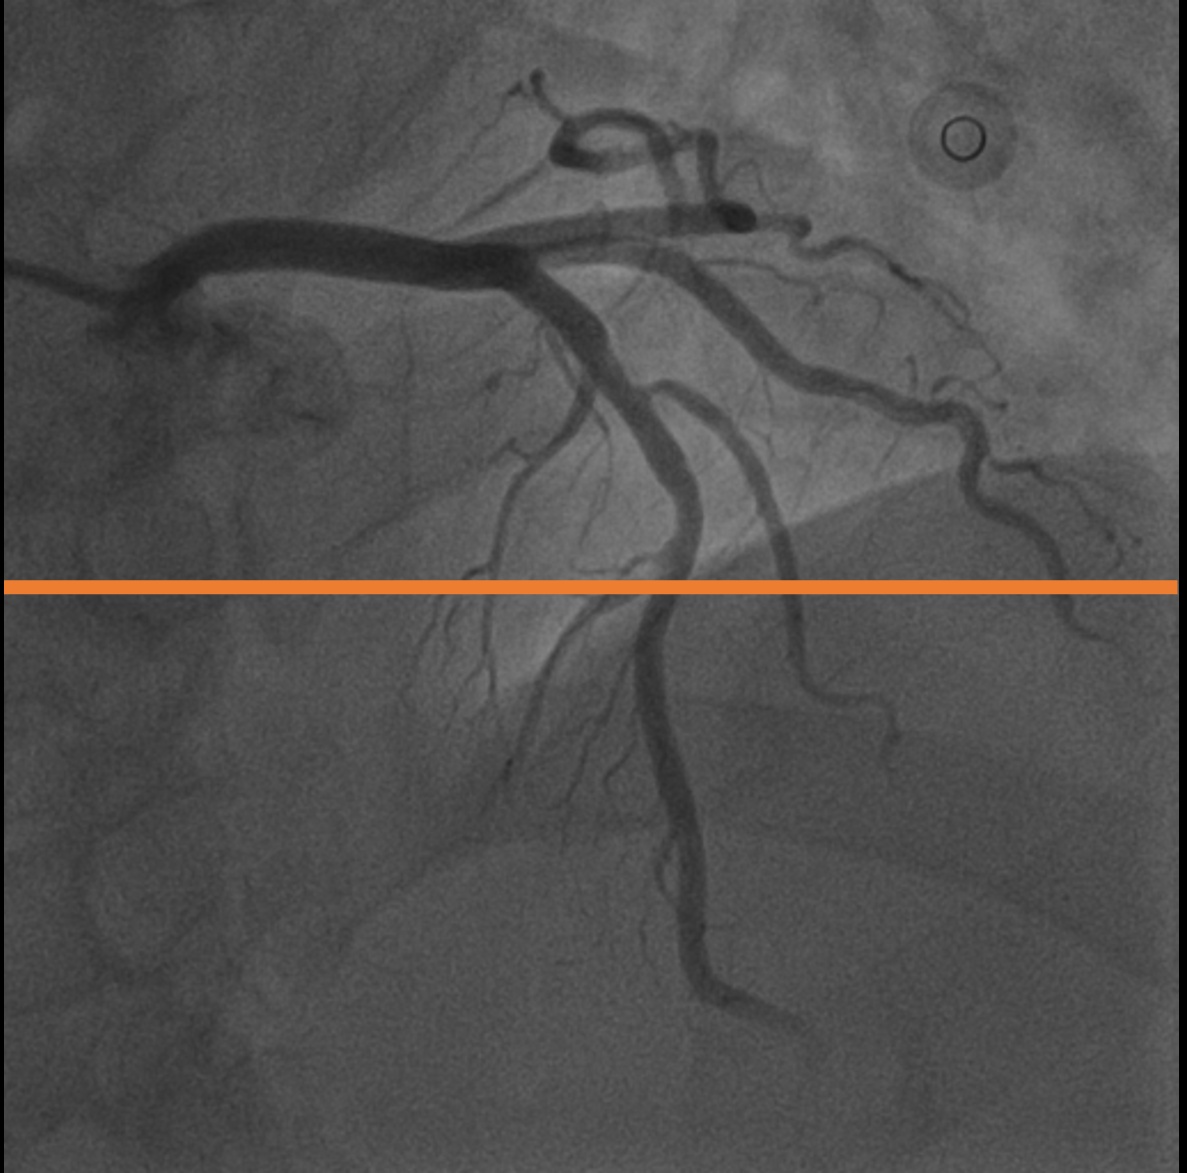

4.1 XACV Dataset

We collect 111 complete records of coronary artery X-ray videos, encompassing the injection, flow through the blood vessels around the heart, and dissipation of the contrast agent. Subsequently, we establish the XACV (X-ray Angiography Coronary Video) dataset. Each video consists of varying numbers of high-resolution coronary artery X-ray images. We invite experienced radiologists to annotate the vascular regions, focusing on one or two frames where the contrast agent is most prominent in each video. The XCAD dataset contains only a single image, and the CADICA video dataset does not provide corresponding ground truth. Therefore, in the following experiments, we conduct all the analyses on our collected XACV dataset and the corresponding GT for each sequence. In Figure 5, we show that compared to other publicly available datasets, XCAD [33] and CADICA [19], our dataset exhibits finer annotations in the vascular regions, providing an advantage for future related tasks. The development and use of our dataset have been approved by our institution’s IRB.